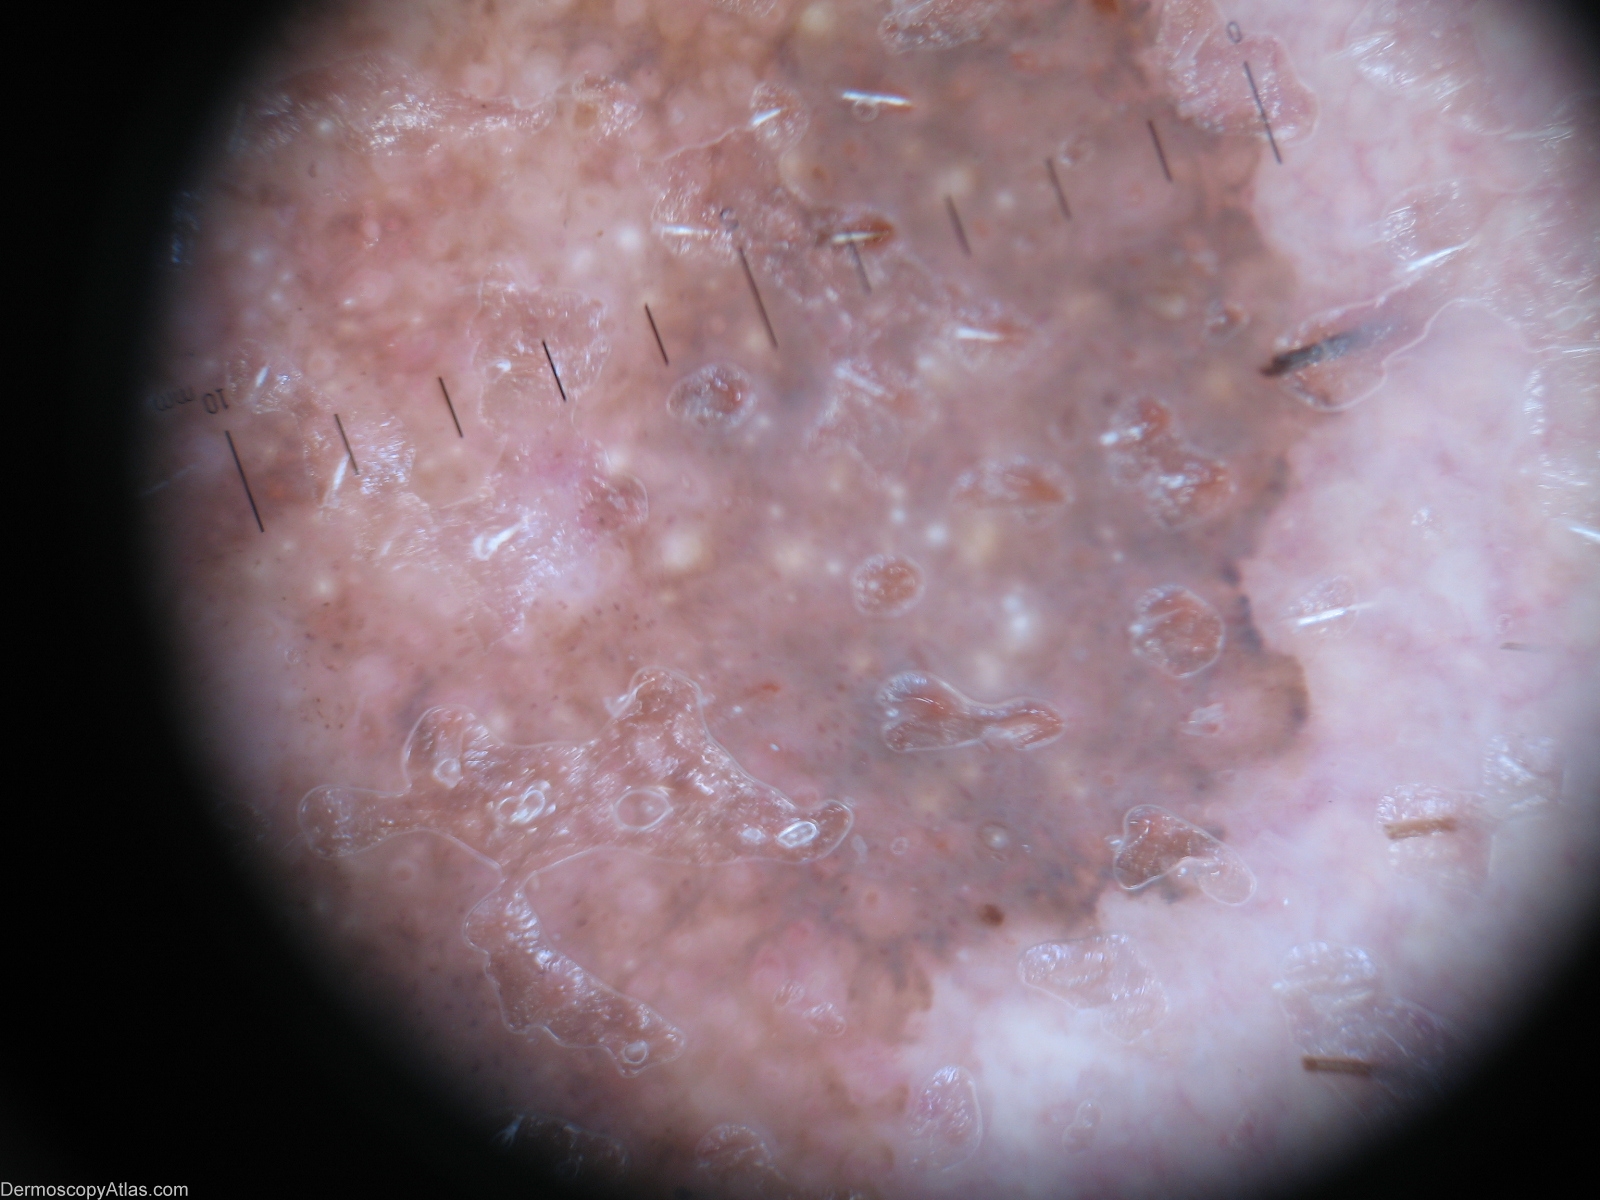

Diagnosis - Solar lentigo

Diagnosis: Solar lentigo